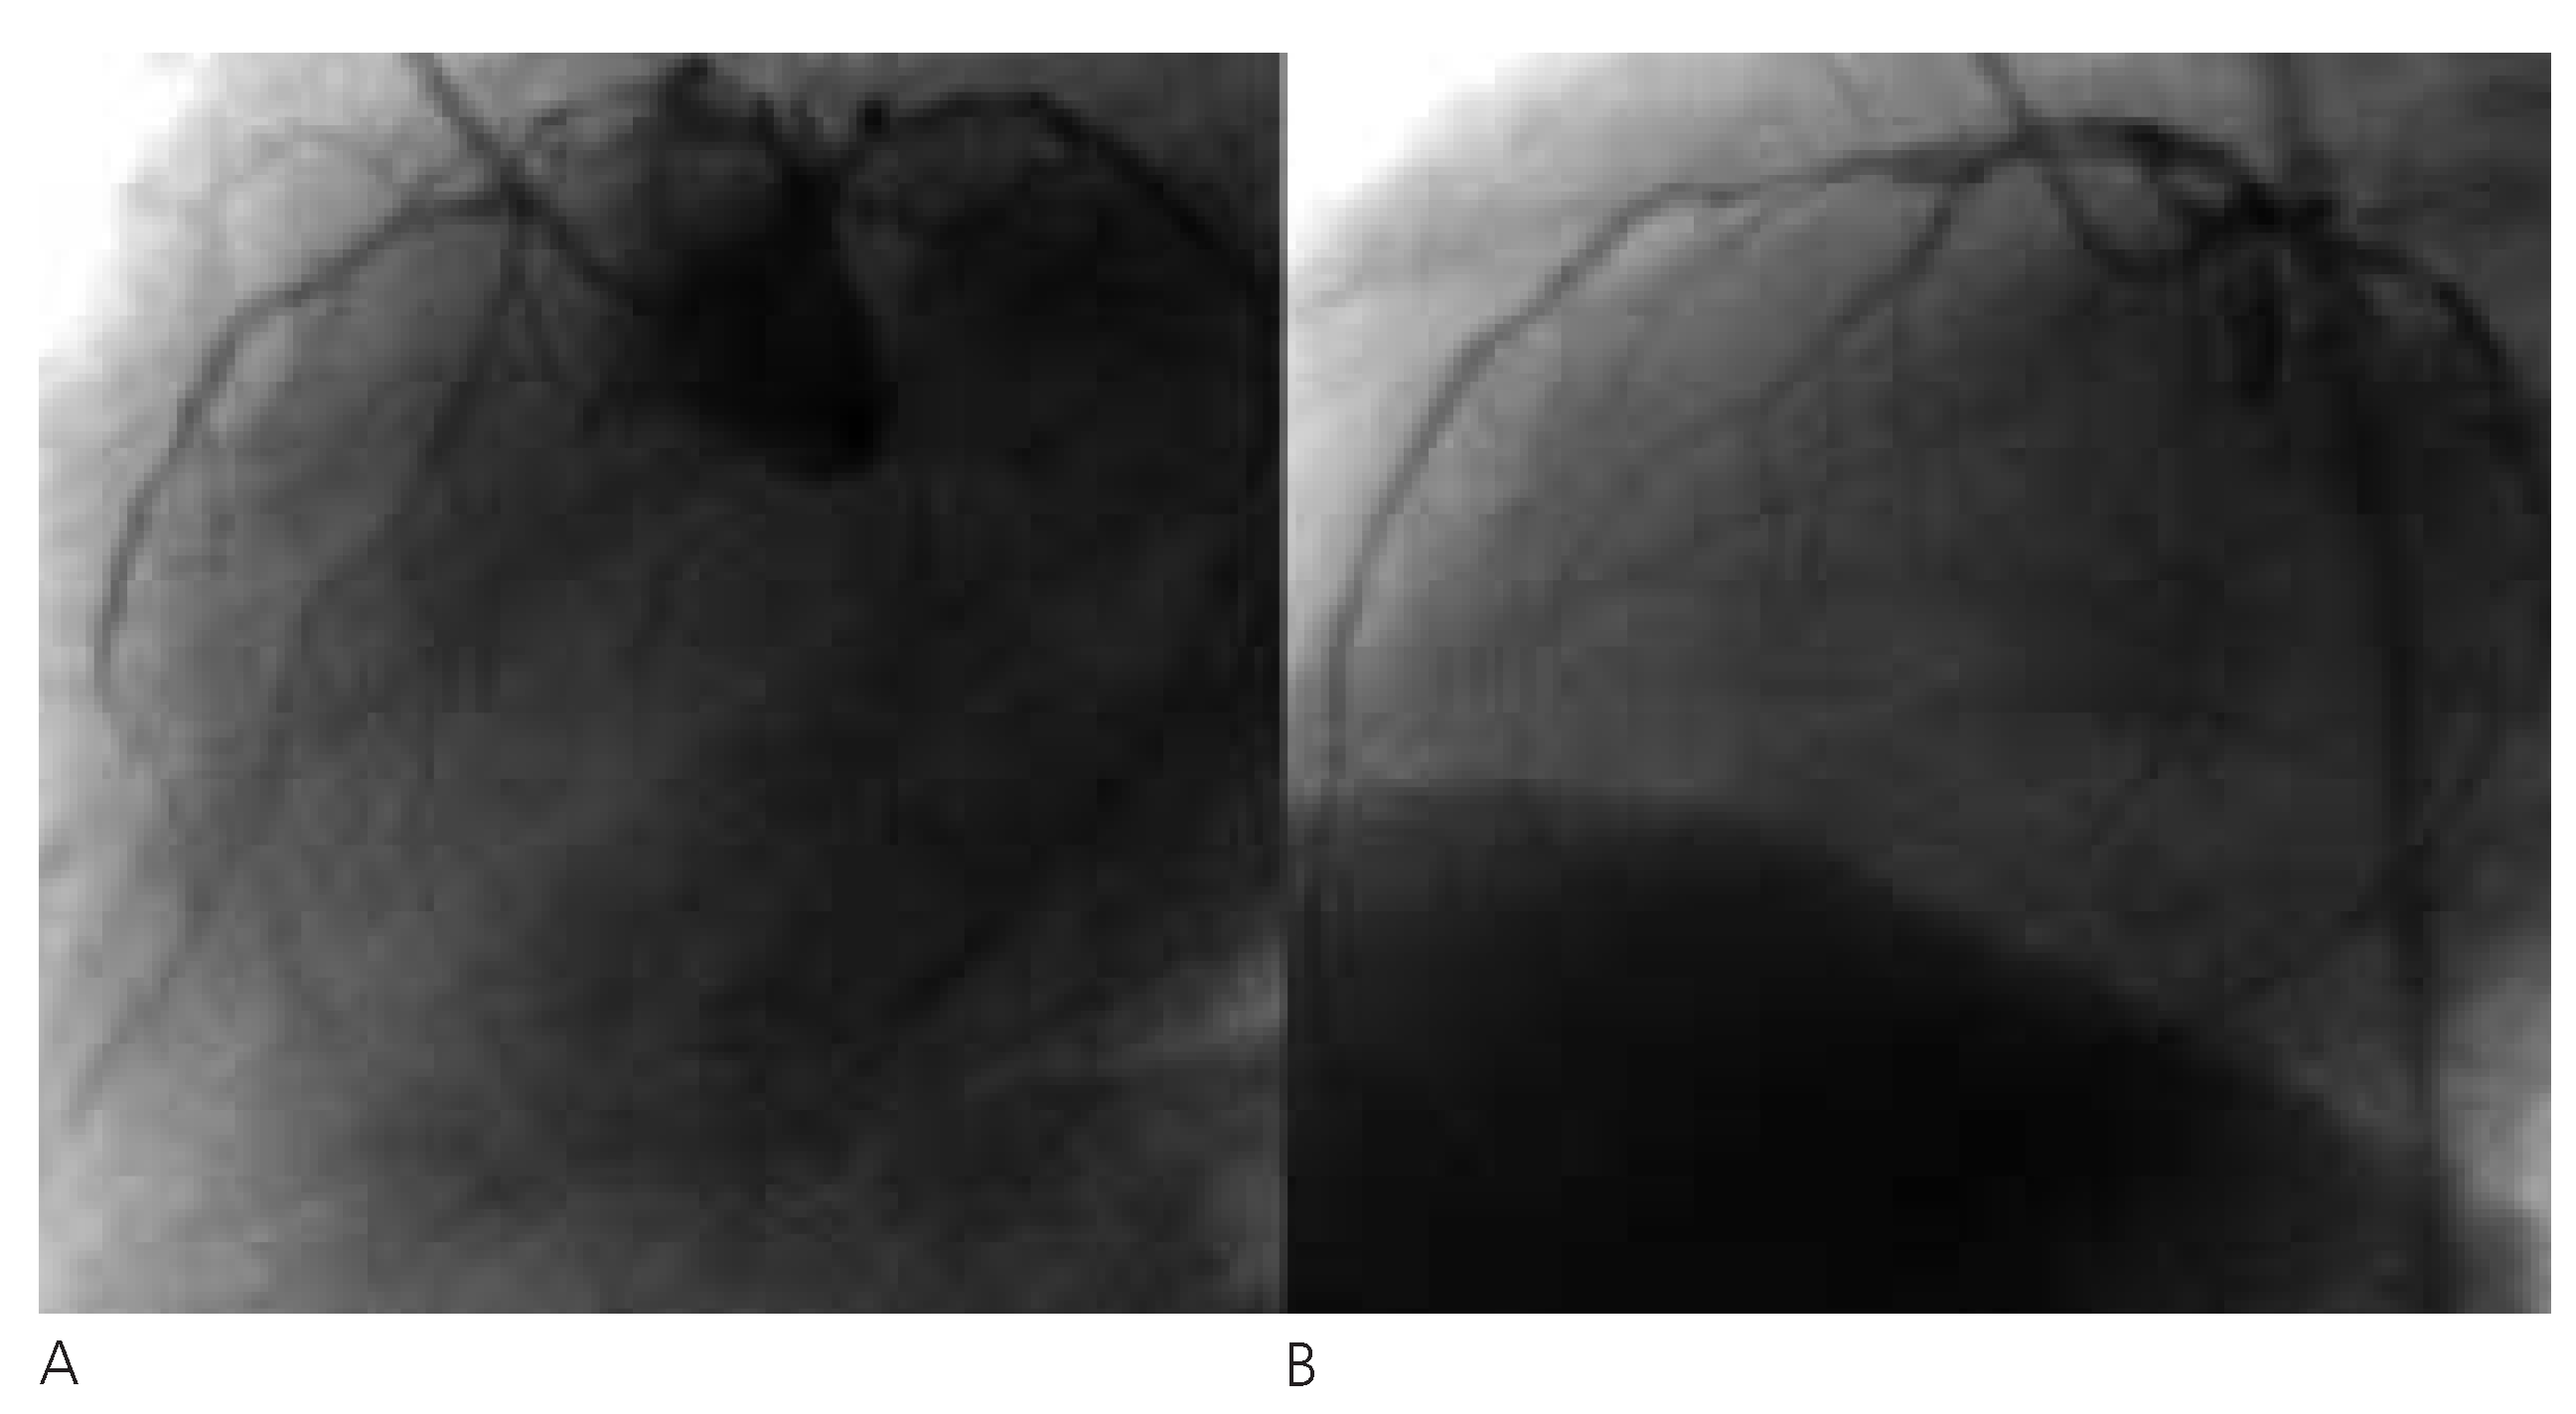

Abbildung 3. Die RIVA-Mitte zeigt nach Stent-Einlage eine <50%-Stenose, der RCX ist proximal 100% verschlossen. Die ACD ist proximal und in der Mitte 75–95% stenosiert (A) und wird erfolgreich gestentet (B).

Cardiovascmed 07 00221 g003